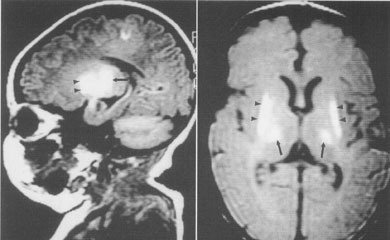

出血多在脐部和消化道,也可在鼻部成肾脏,严重的可发生颅内出血.

新生儿颅内出血